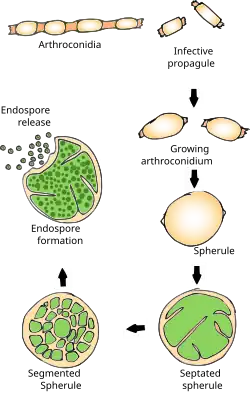

Rain starts the cycle of initial growth of the fungus in the soil.[17] In soil (and in agar media), Coccidioides exist in filament form. It forms hyphae in both horizontal and vertical directions. Over a prolonged dry period, cells within hyphae degenerate to form alternating barrel-shaped cells (arthroconidia) which are light in weight and carried by air currents. This happens when the soil is disturbed, often by clearing trees, construction, or farming. As the population grows, so do all these activities, causing a potential cascade effect. The more land that is cleared and the more arid the soil, the riper the environment for Coccidioides.[18] These spores can be easily inhaled unknowingly. On reaching alveoli, they enlarge in size to become spherules, and internal septations develop. This division of cells is made possible by the optimal temperature inside the body.[19] Septations develop and form endospores within the spherule. The rupture of spherules releases these endospores, which in turn repeat the cycle and spread the infection to adjacent tissues within the infected individual's body. Nodules can form in the lungs surrounding these spherules. When they rupture, they release their contents into the bronchi, forming thin-walled cavities. These cavities can cause symptoms including characteristic chest pain, coughing up blood, and persistent cough. In individuals with a weakened immune system, the infection can spread through the blood. The fungus can also, rarely, enter the body through a break in the skin and cause infection.[19]